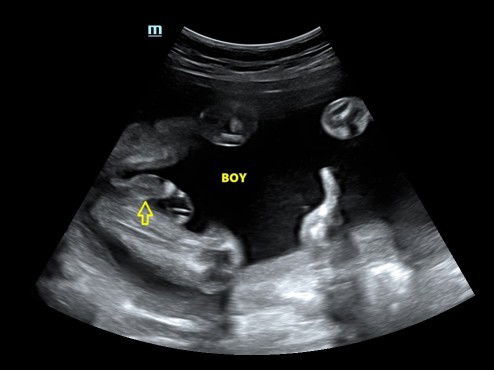

Hai mommies.. Selalunya kalau scan doktor kata boy, nanti keluar sama x? 😅 Ni 2nd baby. Yg 1st girl

Sellau boy memang tepat kalau girl tu ja la ikut nasib bertukar 🤣

Hihi harap betul la boy.. Preparation dh 90% ni beli boy punya 😂 sbb 3x scan, doktor tetap kata yg sama..

Hahahahaha jelas ek pistol 🤣🤣